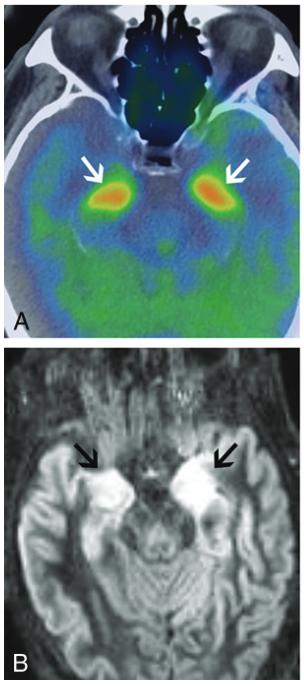

脳:辺縁系脳炎

画像所見

典型的な画像所見は内側側頭葉のT2高信号と腫脹である.時に,造影効果を伴う.FDG-PETでは代謝亢進を認めうる.

他の辺縁系の部位にもこれらの所見が生じることがある(視床下部や乳頭体に明瞭な病変を認め,他の辺縁系は保たれることがある).海馬や扁桃体などの典型的な部分が障害されていない場合でも考慮する必要がある.

治療により画像所見が改善し,FDG-PETでも改善後に代謝低下となる.